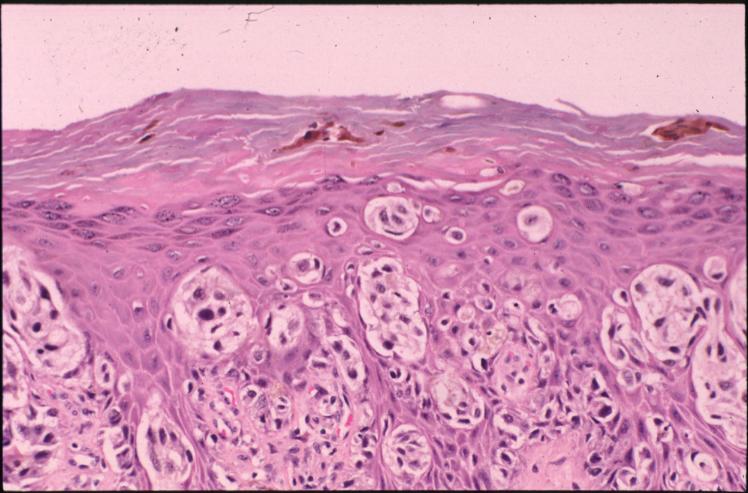

malignant-melanoma